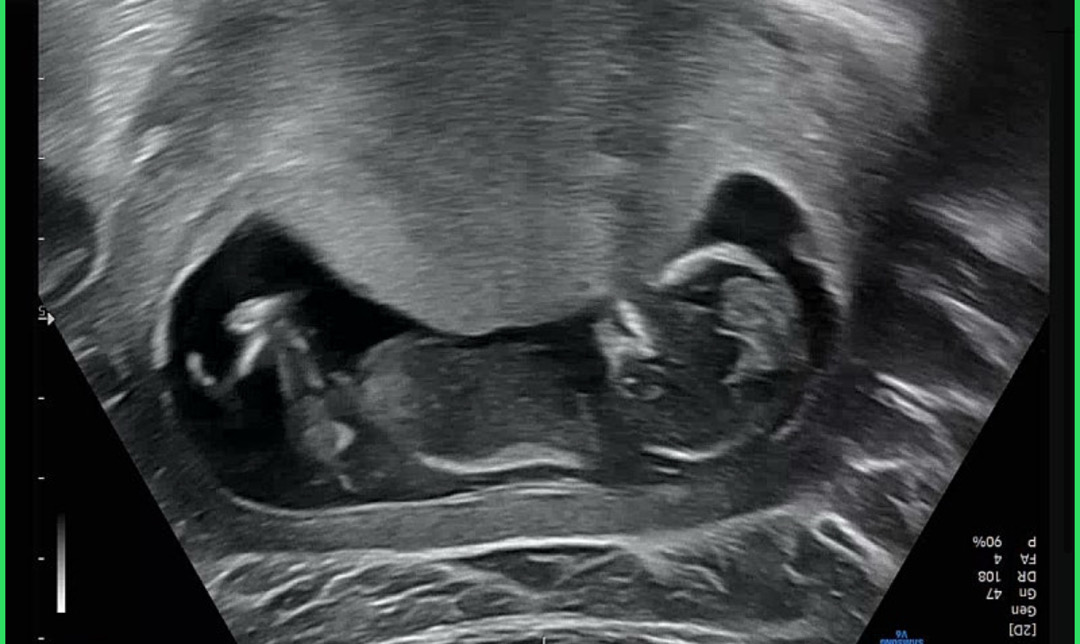

12주에 찍은 초음파입니다 ㅎㅎ 감사합니다 🥹🥹